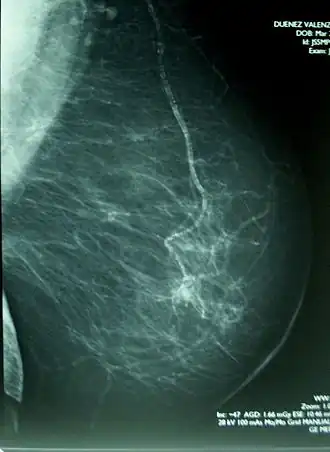

Men spreekt van calcificatie of verkalking, wanneer kalkzouten zich afzetten in levend of dood weefsel. In de geneeskunde spelen verkalkingen in vele organen een rol, zoals de aders, de pijnappelklier en de borst.

Verkalking kan in organismen optreden in littekenweefsel, in gedegenereerd weefsel (dystrofe calcificatie) en in alle weefsels door een te hoog kalkgehalte in het bloed (metastatische calcificatie). Kalk kan zich in plaques afzetten.